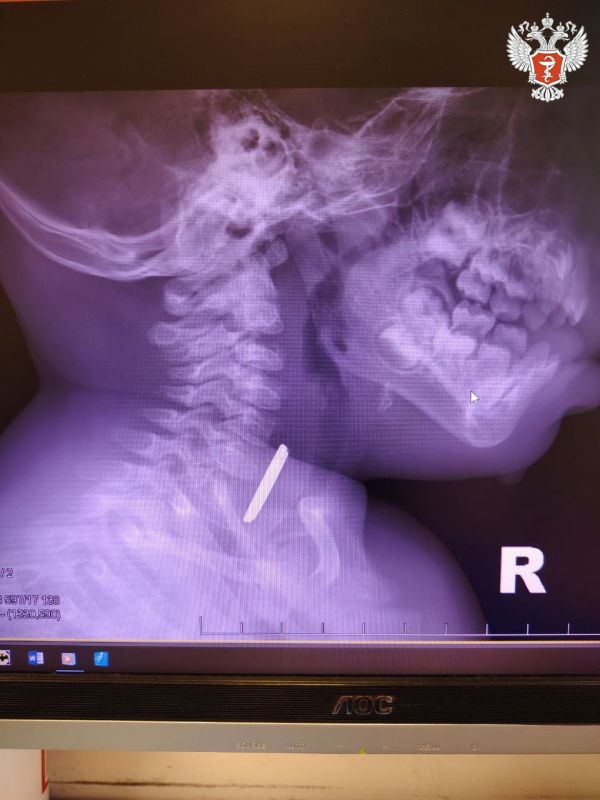

Годовалый ребенок поступил в Нижневартовскую окружную клиническую детскую больницу с затруднённым глотанием и слюнотечением. Врачи выполнили рентген и выявили круглое инородное тело в верхней трети пищевода.Специалисты приняли решение о проведении...